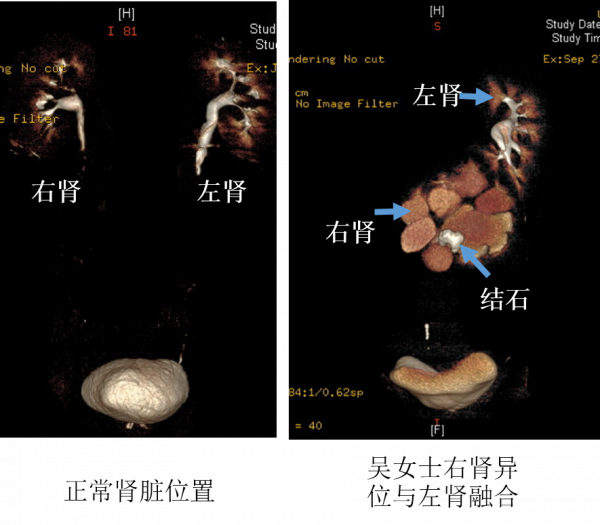

今年51歲的吳女士,3個月前突然感覺自己左側腰腹部疼痛不適,在當地醫院就診後才知道是患上了腎結石,但棘手的是,她還同時被發現是融合腎,本應位於右側的腎臟大部分長在了身體的左側,與左側腎臟下端融合在一起,完全偏離正常位置,解剖結構極為罕見,而腎結石就以散在、多發的形態位於異位的腎臟內。

正常形態的腎臟位於後腰部,在腹腔後方、脊柱的兩側後方。對於腎結石手術,傳統的經皮腎鏡需要經過後腰部穿刺,建立手術通道進行碎石。但吳女士患有結石的異位腎卻位於脊柱及腹腔大血管的前方,從後方穿刺不僅很難建立通道,而且無法觸及結石。腰部手術“行不通”後,在當地醫院的推薦下,吳女士慕名來到清華大學附屬北京清華長庚醫院泌尿外科。